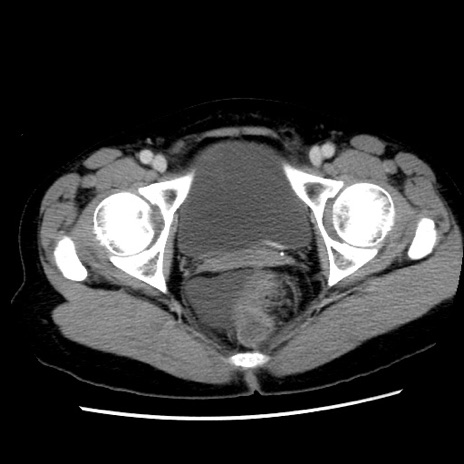

症例10(横断像)

【症例】 50歳代女性

【主訴】 腹痛

【現病歴】前日生レバーを食べた。今朝に排便あり。 昼前に突然発症の腹痛を生じ、当院救急外来を受診した。

【既往歴】 子宮筋腫にてで子宮全摘後

【身体所見】 意識清明、腹部:平坦、軟、下腹部やや左を中心に圧痛・反跳痛あり、筋性防御あり

【データ】WBC 7800、CRP 0.07